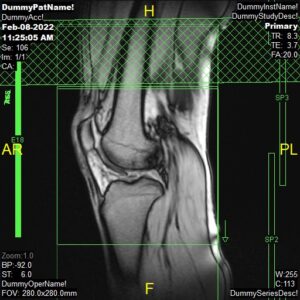

PD Sagittal, PD FatSat Sagittal and T2 Sagittal

Parameters

Sagittal Oblique

Sample Image